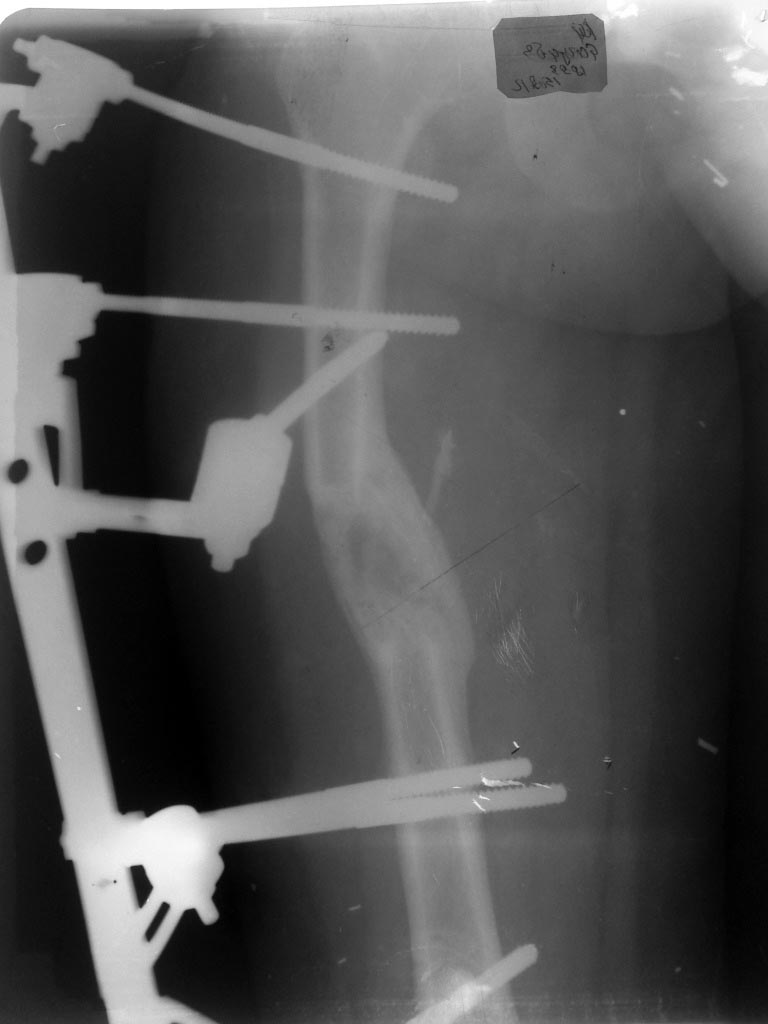

Девочка 13.5 лет, в марте месяце наложили стержневой аппарат МКЦ (произ-во ЦИТО) на бедро в

связи с укорочением бедра на 4.5 см, дистракция до мая месяца на 5.5 см, при наложении аппарата

на проксимальную часть бедра, неправильно были подобраны стержни- короткие, в связи с чем

аппарат перетенул (латерилизовал ) проксимальный отломок, в мае месяце МКЦ констукция для

облегчения была заменена на пластину аппарата Илизарова, попытка медиализировать отломок

мало помогла. сейчас стоит вопрос об удалении стержней. Можно ли при таком смещении это

делать ведь фактически смещение по ширине а не под углом, ? при полной нагрузке не

сформируется ли угловая деформация бедра, хотя консолидация хорошая, клинически, ось

бедра правильная и симметрична другой ноге.